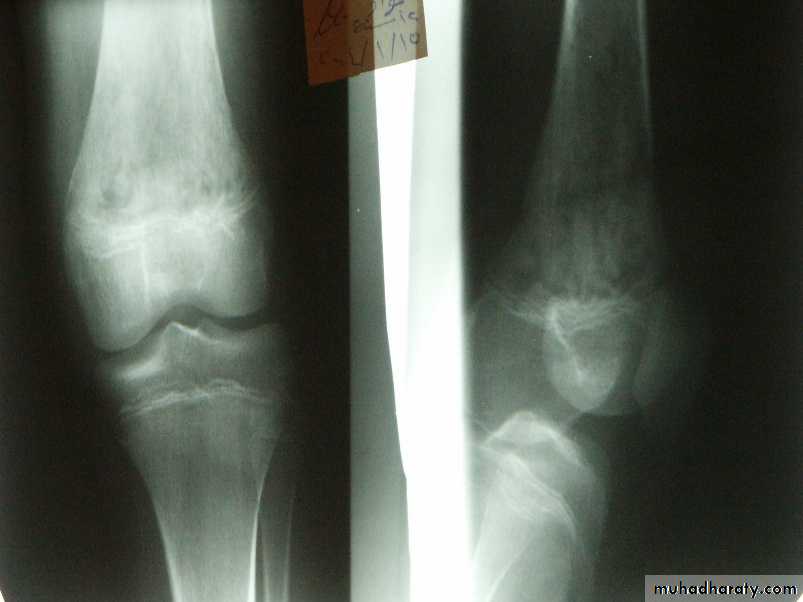

X-ray finding:

x-ray films are negative within 1-2 weeks,Although carefully comparison with the opposite side may show abnormal soft tissue shadows.

It must be stressed that x-ray appearances are normal in the acute phase. There are little value in making the early diagnosis.

Radiography not appear till after 3 weeks.

decrease bone density moth eaten.later on new bone formation.